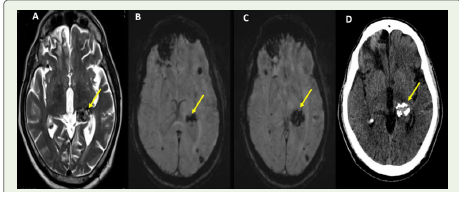

The screening MRI of the brain revealed multiple cavernous

malformations of bilateral cerebral hemispheres [Figure 2A-D].

Figure 2:MRI of the brain showed lesions of mixed signal intensities on

T2-sequence (A) and blooming on SWI sequences (B, C) suggestive of

multiple intra-cerebral cavernous malformations. CT-brain (D) showed the

characteristic popcorn calcifications associated with cavernous malformations.